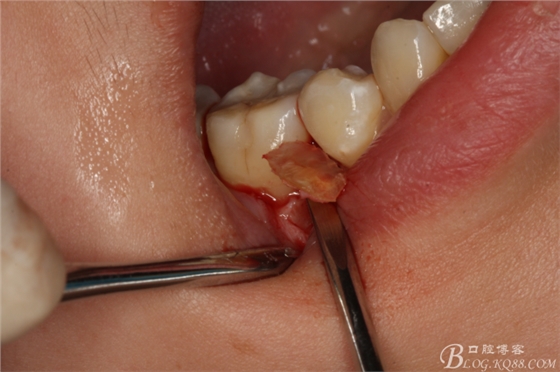

圖5.局部麻醉下、在44近中做垂直小切口,切口不要超過膜齦聯(lián)合。